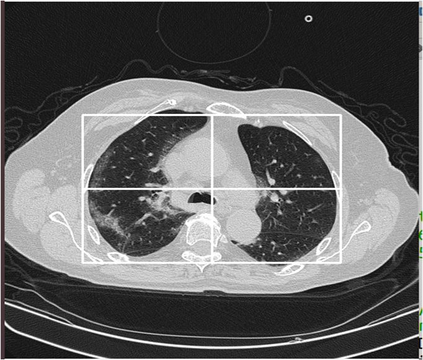

The paper represents a method of a Convolution Neural Networks (CNN) model for image classification with image preprocessing and hyperparameters tuning, aiming at increasing the predictive performance for COVID-19 diagnosis while avoiding deeper and thus more complex alternatives. Firstly, the CNN model includes four similar convolutional layers followed by a flattening and two dense layers. This work proposes a less complex solution based on simply classifying 2D slices of CT scans using a CNN model. Despite the simplicity in architecture, the proposed CNN model showed improved quantitative results exceeding state-of-the-arts on the dataset of images, in terms of the macro F1 score. The results were achieved on the original CT slices of the dataset. Secondly, the original dataset was processed via anatomy-relevant masking of slices, removing non-representative slices from the CT volume, and hyperparameters tuning. For slice processing, a fixed-sized rectangular area was used for cropping an anatomy-relevant region of interest in the images, and a threshold based on the number of white pixels in binarized slices was employed to remove non-representative slices from the 3D-CT scans. The CNN model with a learning rate schedule with exponential decay and slice flipping techniques was deployed on the processed slices. The proposed method was used to make predictions on the 2D slices. For final diagnosis at a patient level, majority voting was applied on the slices of each CT scan to make the diagnosis. The macro F1 score of the proposed method well exceeded the baseline approach and other alternatives' scores on the validation set as well as on a test partition of the previously unseen images from the COV19-CT-DB dataset partition.